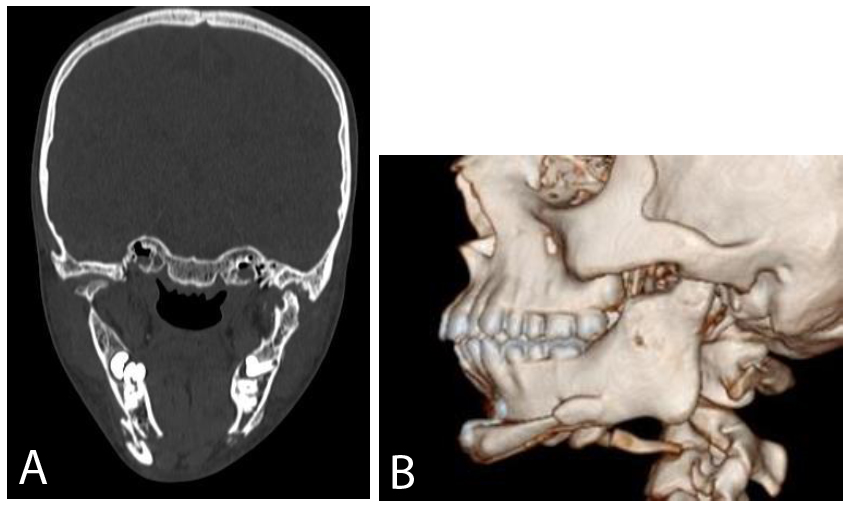

The patient was recalled for regular follow-up visits, during which the mouth opening gradually increased, and the surgical site was found to be healthy with no signs of dehiscence, gapping, collection, or discharge (Fig. 6A-B).

CT scans A. Coronal view, B. 3DCT.

The patient’s facial profile also improved, and mouth opening gradually increased to 40 mm at the 1-year follow-up visit (Figs. 7A-B and 8, respectively).